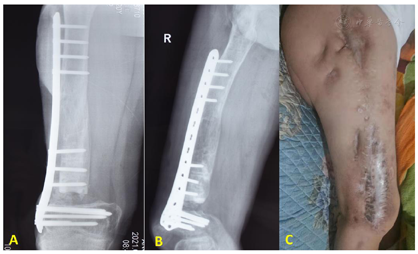

患者男性,17岁,因"右侧股骨反复流脓10年"入院。患者诉10年前无明显原因出现高热,继而出现右大腿疼痛、肿胀。当时到当地医院就诊,诊断为:"右股骨血源性骨髓炎",行股骨开窗减压、冲洗引流治疗,病情好转后出院,十年间患者反复多次出现发作,经过输抗生素治疗后有所缓解,病情时好时坏,期间多次到当地医院及省会某医科大学附属医院进行骨髓炎手术治疗(具体手术方案不详,共10次手术),一直无法根治,且逐渐出现髋膝关节僵直,活动障碍,2019年再次复发来我院就诊(见图1A),予病灶清创,碘纺纱条填塞治疗,治疗后感染得到控制(见图1B)。术后1年半大腿远端再次复发入院(见图1C)。入院查体:一般情况及全身情况良好,生命体征平稳,行走跛行,右侧髋膝关节僵直,活动障碍,右股骨上段外侧可见陈旧性手术瘢痕,愈合良好,局部无红肿及压痛,无叩击痛,右股骨中下段外侧可见约4cm*0.8cm窦道,深达股骨髓腔,窦道内有流脓,周围稍红肿,压痛及叩击痛明显,无高血压、糖尿病等病史,无过敏史,无冶游史,家族中无遗传病病史。